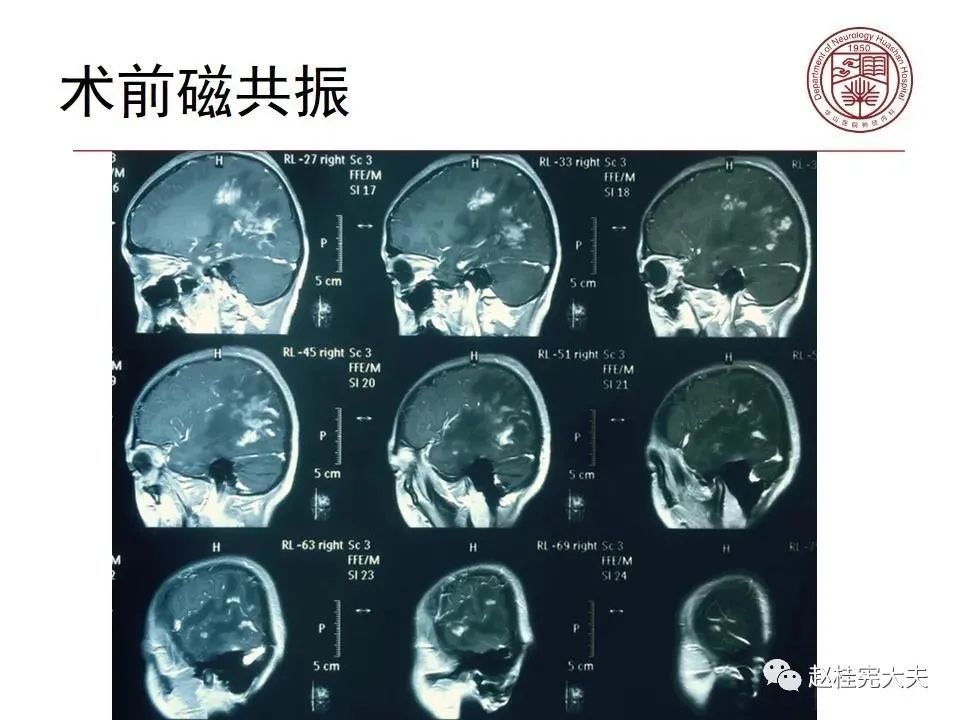

患者女性,19岁,反复头痛数年,近期加重伴记忆力下降,反复查磁共振报正常。结合病史,仔细阅片发现大脑皮层Flair、DWI异常信号。抽血查血清MOG抗体1:32,诊断MOG皮层脑炎。